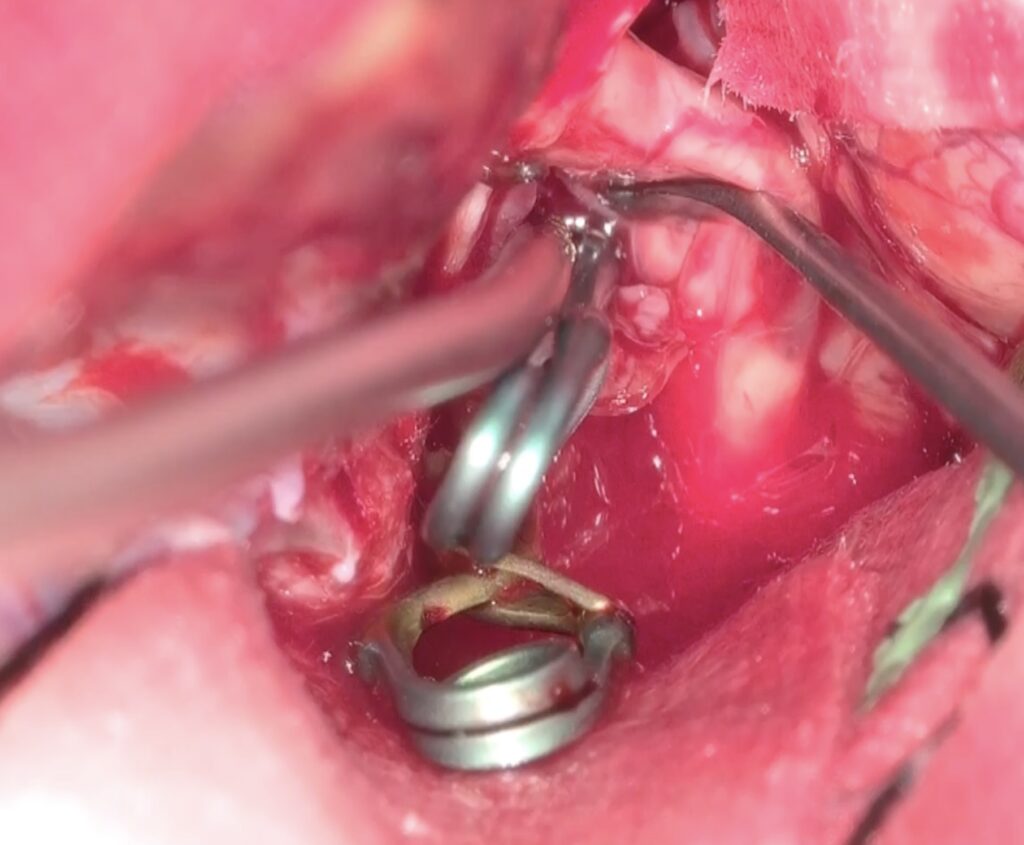

最近のこの場所の動脈瘤クリッピング術が増えています。4mm以上の上向き動脈瘤で術前BTOで虚血耐性のあるものを適応としています。ICG、MEP、VEG、術中血管撮影など術中画像、電気生理学モニタリングをしっかり準備して行っています。本例も視神経下面と癒着しており、剥がすときに破れましたが、問題なくクリップできています。術後の視機能も良好でした。

術後嗄声と2/23より髄液鼻漏れがあり、CTで左篩骨洞に髄液貯留があり5日間の腰椎ドレナージを行い、治癒しました。